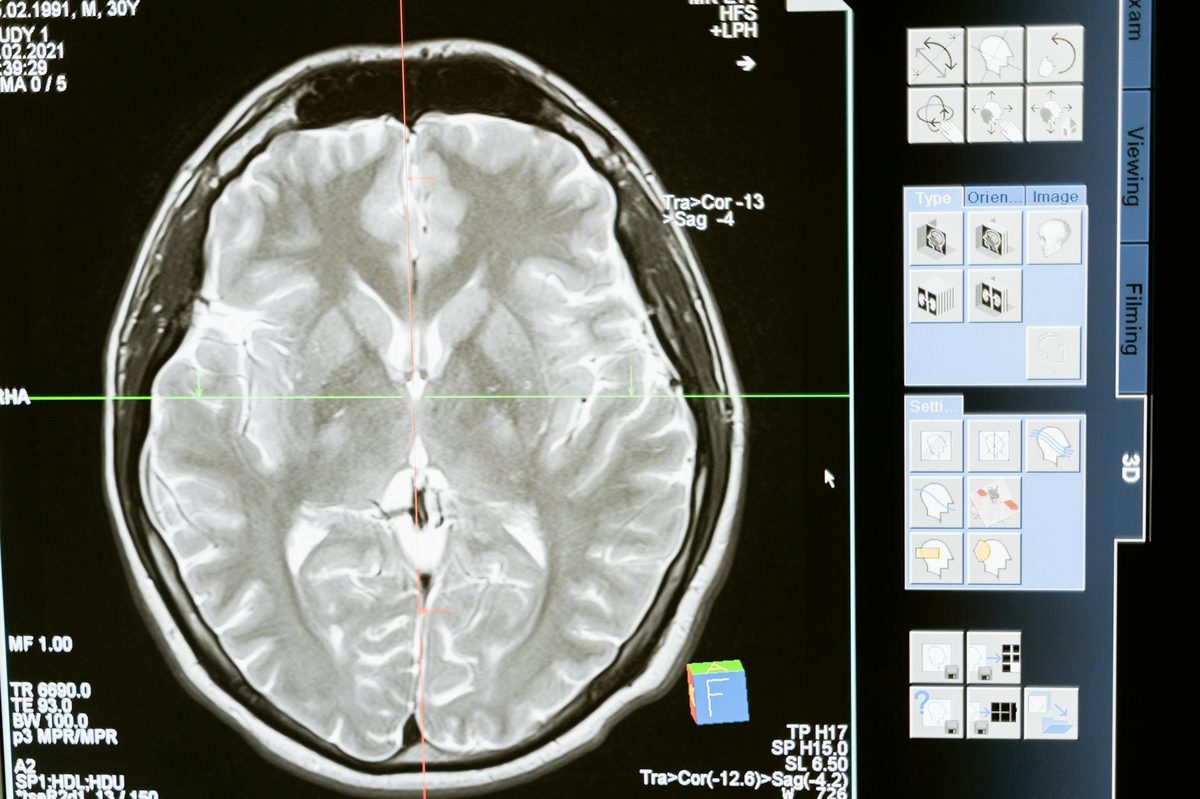

The failure demonstrated that AI trained on hypothetical cases and medical literature could not generalize to real patients. Modern AI systems like Prima train on actual clinical data, learning from how physicians actually diagnose rather than how textbooks describe disease.

Prima's approach—training on 200,000 real MRI studies with physician diagnoses—directly addresses Watson's central failure. The system learns from actual clinical practice rather than synthetic cases or literature abstracts.